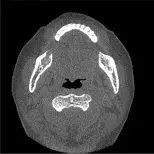

- 原始影像(左上):為一張頭部軸切面(Axial)CT 影像,可見上頜骨、下頜骨、牙齒與呼吸道等解剖構造,具備完整的灰階與對比度。

- 選項 B:外觀幾乎與原始影像相同,保有完整的低頻對比度與高頻細節,未見明顯的低頻濾除現象。